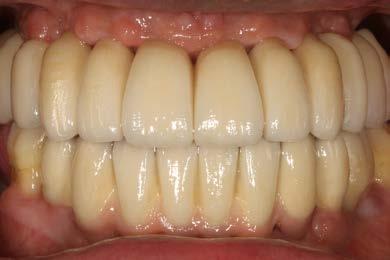

14 y 15. Imágenes inicial y tras el seguimiento de 4 años del paciente. Vemos

Figura 13. Radiografía tras la colocación de las prótesis definitivas en el paciente.

Figuras

cómo ha cambiado completamente la oclusión, la estética y la salud de los tejidos gingivales.

correcta en los movimientos masticatorios. Mantener piezas dentales nos posibilita la consecución de una propiocepción efectiva y aumenta del valor que tiene para un paciente desde un punto de vista psicológico la conservación de parte de su dentición natural.15-16,22 Una vez finalizada la rehabilitación protésica, el paciente continúa en seguimiento activo, con mantenimiento periodontal y periimplantario, inicialmente cada 3 meses y posteriormente al año de seguimiento espaciando las visitas de control cada 6 meses. Durante todo el seguimiento (4 años) la estabilidad ósea entorno a los implantes dentales, se mantiene estable, así como en los molares remanentes (Figura 13-16). Ambas técnicas por lo tanto (elevación transcrestal y elevación de seno convencional) han obtenido un resultado muy similar por lo tanto en el paciente reportado, con EP

agresiva, siendo buenas opciones de tratamiento, aunque cada una con sus indicaciones en función del volumen óseo residual como hemos comentado en el inicio del artículo.